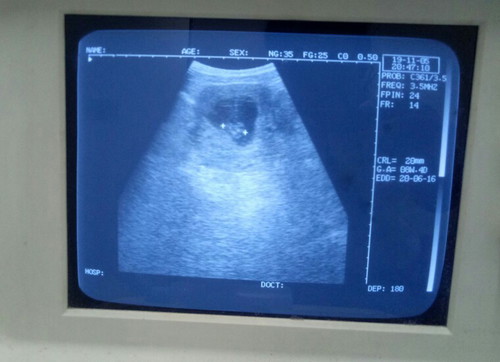

ผลอัลตร้าซาวด์ 7 Week 6 day

เห็นหัวใจดวงน้อยๆเต้นแล้ว ดีใจสุดๆ ตอนแรกกังวลเหมือนกันว่าจะยังไม่เจอน้อง เพราะอายุครรภ์ยังน้อยมาก หมอบอกว่าตอนนี้ตัวอ่อนมีหัวใจแล้ว ขนาดความยาว 2 ซม. อิแม่โล่งใจเลยจ้าา❤